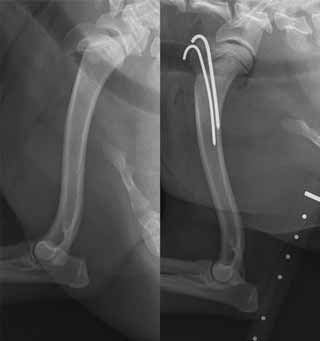

Growth plate (physeal) fractures

Growth

plates are cartilage plates on each end of long bones, such as the leg

bones (radius and ulna), in the dogs' body. It is the region of

the bone of young, growing dogs, which lengthens the bone as the dog

grows. The plates continue to grow until the bones reach the adjoining

joints, at which point the growth plates "close" and the bones stop

enlarging.

In

the x-ray at the right, the forelimb of a 9 week old puppy shows growing

radius and ulna bones which are not yet connected to the elbow and

wrist. A growth plate is at each end of these bones. Once the bones

connect with adjoining bones, the growth plates close and become fused

at an epiphyseal line. (See diagram at the left.)

Growth plates close at different ages for dogs of different breeds, and even in individual dogs, some of their growth plates close before others. For example, typically the ulna plates close before the adjoining radius plates.

Fractures

of the bones of immature dogs can include a growth plate (physis),

called a physeal fracture. A

hazard

of damaging and/or repairing a growth plate is that it could

cause premature closure of the plate. Degrees of growth plate fractures

are classified by the Salter-Harris classification system (see

diagram at right).

In a February 2016 article, UK orthopedists discuss a growth plate (Salter-Harris type I) fracture of the humerus of a cavalier King Charles spaniel. The radiograph photos in the linked article show the CKCS at left with the fracture and at right how it has been stabilized with parallel K-wires through the greater tubercle into the humeral diaphysis.

Care should be taken to not allow cavalier puppies to engage in strenuous physical activities, such as jumping from high heights (even from furniture to floor) before their growth plates close.